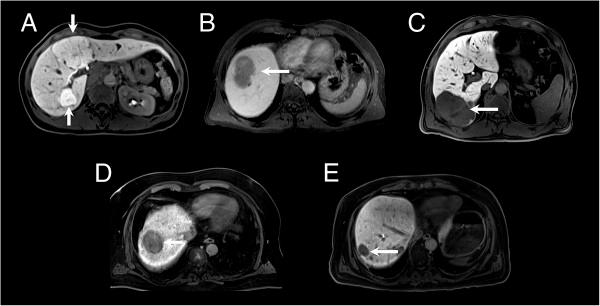

Correct characterization of focal solid hepatic lesions has always been a challenge and is of great diagnostic and therapeutic relevance. The purpose of this study was to determine the added value of hepatobiliary phase images in Gd-EOB-DTPA-enhanced magnetic resonance imaging (MRI) for differentiating focal solid hepatic lesions.

METHODS

In this retrospective trial 84 consecutive patients underwent Gd-EOB-DTPA-enhanced MR examinations. MRI was conducted for 64 patients with malignant focal hepatic lesions (34 hepatocellular carcinoma (HCC), 30 metastases) and for 20 patients with benign hepatic lesions (14 focal nodular hyperplasia (FNH), 3 adenoma, 3 hemangioma). Five radiologists independently reviewed three sets of MR images by means of a 5-point confidence scale from score 1 (definitely benign) to score 5 (definitely malignant): set 1: unenhanced images; set 2: unenhanced and Gd-EOB-DTPA-enhanced dynamic images; set 3: hepatobiliary phase images in addition to set 2. Accuracy was assessed by the alternative free-response receiver operating characteristic curve (Az) and the index of diagnostic performance was calculated.

RESULTS

Diagnostic accuracy was significantly improved by the addition of Gd-EOB-DTPA-enhanced dynamic images: Az in set 1 was 0.708 and 0.833 in set 2 (P = 0.0002). The addition of hepatobiliary phase images increased the Az value to 0.941 in set 3 (set 3 vs set 2, P < 0.0001; set 3 vs set 1, P < 0.0001). The index of diagnostic performance was lowest in set 1 (45%), improved in set 2 (71%), and highest in set 3 (94%).

CONCLUSIONS

Hepatobiliary phase images obtained after Gd-EOB-DTPA-enhanced dynamic MRI improve the differentiation of focal solid hepatic lesions.